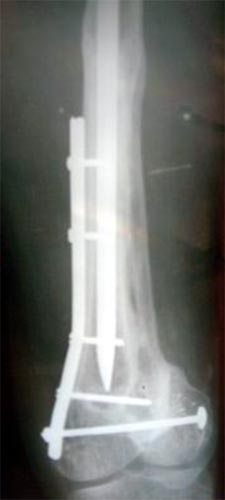

病例二、患者62岁,股骨中1/3骨折骨不连2年,3次钢板手术失败,明显畸形。

同上述方法治疗,9个月后骨折愈合。